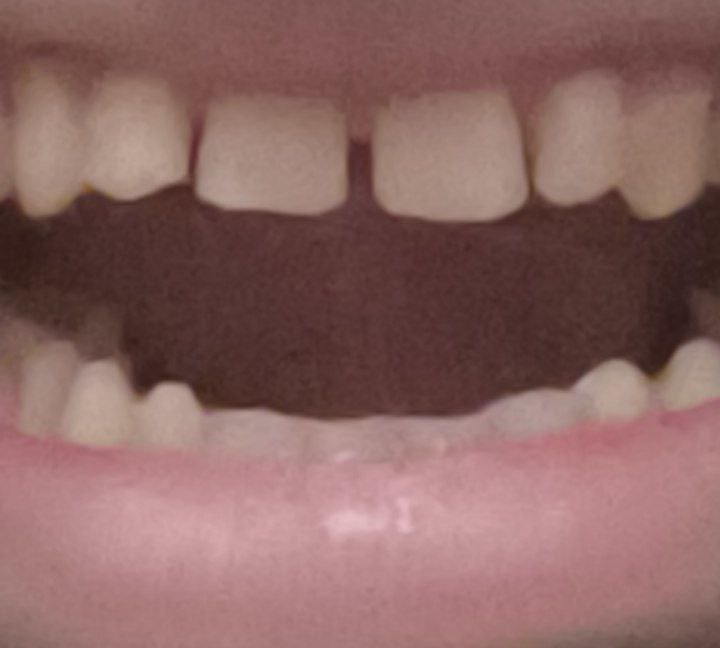

1000070961.jpg 180Кб, 882x704

882x704

Зуб пятерка. Возможно такое вылечить, анонче? Отклолся как то, вообще не болит.